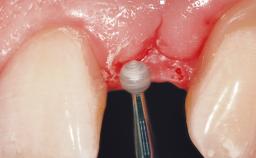

Late Flapless Placement of an Implant in a Maxillary Left Central Incisor Site

A 39-year-old male patient presented with a chief complaint of discomfort and gingival discoloration around his maxillary left central incisor. He was in good general health and was a non-smoker. His past dental history was significant because of the traumatic fracture of tooth 21 in a sporting accident at age 13. Initial dental treatment included endodontic therapy and a full-coverage restoration. The patient became symptomatic 5 years later, when structural failure of the tooth resulted in the dislodgment of the crown. Endodontic retreatment, apical surgery, and post-and-core restoration were performed.

Soft Tissue Grafting Simultaneous

Soft Tissue Anatomy Intact Defective

Soft Tissue Contour and Volume Slightly compromised